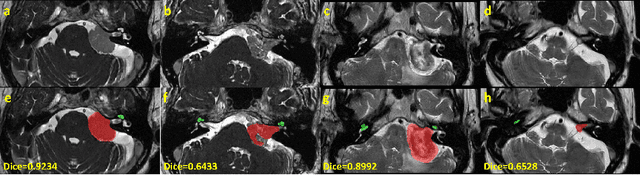

Automatic segmentation of vestibular schwannoma (VS) and the cochlea from magnetic resonance imaging (MRI) can facilitate VS treatment planning. Unsupervised segmentation methods have shown promising results without requiring the time-consuming and laborious manual labeling process. In this paper, we present an approach for VS and cochlea segmentation in an unsupervised domain adaptation setting. Specifically, we first develop a cross-site cross-modality unpaired image translation strategy to enrich the diversity of the synthesized data. Then, we devise a rule-based offline augmentation technique to further minimize the domain gap. Lastly, we adopt a self-configuring segmentation framework empowered by self-training to obtain the final results. On the CrossMoDA 2022 validation leaderboard, our method has achieved competitive VS and cochlea segmentation performance with mean dice scores of 0.8178 $\pm$ 0.0803 and 0.8433 $\pm$ 0.0293, respectively.